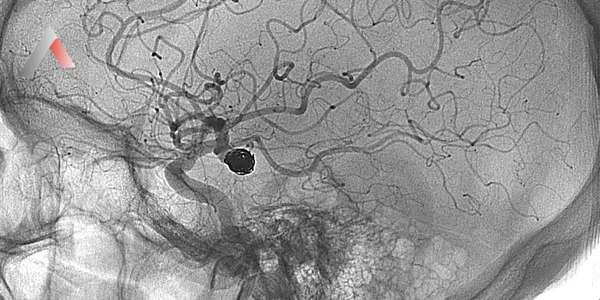

• BT anjiografi veya MR anjiografi: Beyin damarlarını görüntülemek ve tıkanıklığı tespit etmek için kullanılır.

• Mekanik trombektomi: Bu yöntemde, beyin damarlarını tıkayan kan pıhtısı, kateter adı verilen ince bir tüp yardımıyla çıkarılır. Mekanik trombektomi, trombolitik tedaviye uygun olmayan veya trombolitik tedaviye yanıt vermeyen hastalarda uygulanabilir.